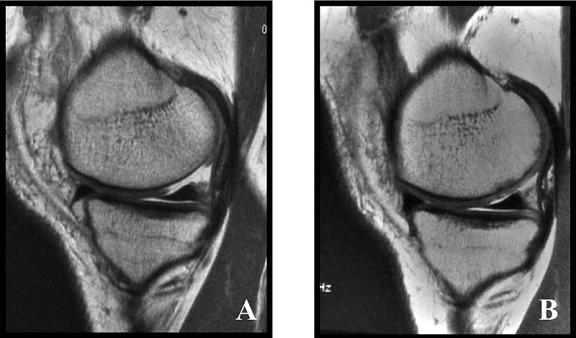

1. Imaginile RMN

Din 48 de pacienti tratati cu tehnica de microfracturare in studiul nostru , 24 (50%) au acceptat sa fie evaluati prin imagini ale rezonantei magnetice. RMN a fost facuta doar pentru studiu si nu datorita vreunui simptom clinic si s-a efectuat in medie la 12 2 luni (de la 3 la 36 de luni) dupa operatie. Imaginile au fost executate la mai putin de 6 luni pentru 3 pacienti (13%), de la 6 la 12 luni pentru 15 pacienti (61%) si mai mult de 12 luni dupa microfracturi pentru 6 pacienti (26%). Sase pacienti au o serie de imagini RMN cu media 1,3 0,1 (de la 1 la 3 scanari) pe pacient. La acesti 6 pacienti, descoperirile la cea mai recenta evaluare imagistica au fost folosite pentru analiza rezultatelor functionale. Nu s-au gasit diferente semnificative intre pacientii cu sau fara evaluare imagistica RMN cu privire la datele demografice (p> 0,650); caracteristicile leziunilor (p>0,450); durata preoperatorie a simptomelor (p= 0,793); indexul masei corporale (p= 0,217); durata urmarii postoperatorii (p= 0,902); si scorul preoperator si postoperator pentru activitatile zilnice(p=0,250); SF-36componenta fizica (p= 0,250), IKDC (p= 0,820) si rata subiectiva (p = 0,867).

Fig.34. A-scanare inaintea microfracturarii, B-scanare la patru luni dupaa microfracturare.

Evaluarea imaginilor RMN a fost realizata de catre radiologist cu experienta, care cunostea situatia pacientilor si operatia efectuata. Imaginile au fost astfel analizate incat sa se observe zonele cu cartilaj de reparare comparativ cu cel nativ. Repararea morfologica a fost descrisa ca depresiva, neteda, sau mareata comparativ cu cartilajul nativ inconjurator. Volumul de umplere al defectului cu cartilaj reparator a fost masurat folosind imagini sagitale si coronale si a fost gradat ca bun (intre 67% si 100%), moderat (34% la 66%), sau slab (0% la 33%) pe baza procentajului defectului umplut. Interfata cu suprafata cartilajului nativ adiacent a fost evaluata si gradata ca fiind mica ( gaura ≤ 2mm) sau mare (gaura ˃ 2mm). Edemul maduvei osului subcondral a fost gradat ca fiind usor (˂ 1 cm²), moderat (intre 1 si 3 cm²) sau sever (˃ 3 cm²), iar prezenta sau absenta cresterii osoase a fost atent inregistrata.

Imaginile rezonantei magnetice au demonstrat un semnal hiperintens al cartilajului reparator la 22 de pacienti (92%) din cei 24 si usoare edeme subcondrale la 17 pacienti (71%). Umplerea cu cartilajul reparator a fost clasificata ca fiind buna ( 67% la 100%) la majoritatea pacientilor, dar cele mai multe leziuni tratate demonstreaza deprecierea morfologiei cartilajului reparator in cartilaj hialin adiacent. Pentru 6 pacienti au fost disponibile RMN-uri secventiale si toate au demonstrat cel putin un grad de umplere moderat.Nu au existat deteriorari al volumului de umplere la acesti pacienti, dar un pacient a avut o crestere a volumului de umplere in timp. Nu s-a gasit o corelare statistica intre volumul cartilajului reparator si timpul scurs de la microfracturi ( r = 0,173; p = 0,420). Cresterea osoasa a fost demonstrata la sase pacienti (25%). Doua treimi din acestia au avut un grad bun de umplere. Toti cei 13 pacienti cu un bun grad de umplere au avut o imbunatatire a scorului activitatilor zilnice, pe cand doar 3 pacienti cu umplere moderata a defectului si doar unul cu slaba umplere au avut o crestere a acestui scor (p < 0,05). Similar, scorul componentei fizice SF-36 si rata subiectiva a crescut semnificativ la pacientii cu un grad bun de umplere observat in imaginile rezonantei magnetice (p < 0,05). Descresterea scorului functional dupa 24 de luni a fost observata la toti pacientii cu un slab grad de umplere dupa microfracturi, pentru 2 pacienti cu un grad moderat de umplere (p= 0,097) si pentru 3 pacienti cu grad bun de umplere (p < 0,05). Scorul activitatilor zilnice (p < 0,05; r = 0,385) si scorul componentei fizice SF-36 (p ˂ 0,05; r = 0,388) obtinute in timpul rezonantei magnetice demonstreaza o corelatie statistica pozitiva cu gradul de umplere.